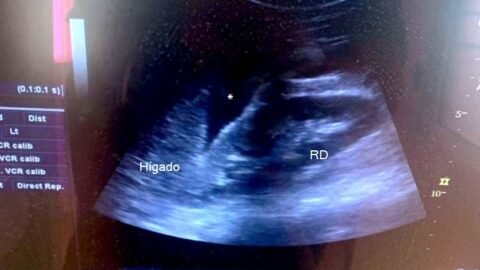

POCUS #21: diagnóstico rápido Paciente embarazada ingresa a la guardia durante la madrugada en mal estado general. Al examen...

POCUS: point-of-care ultrasound

Imágenes de ultrasonido para responder preguntas clínicas concretas.